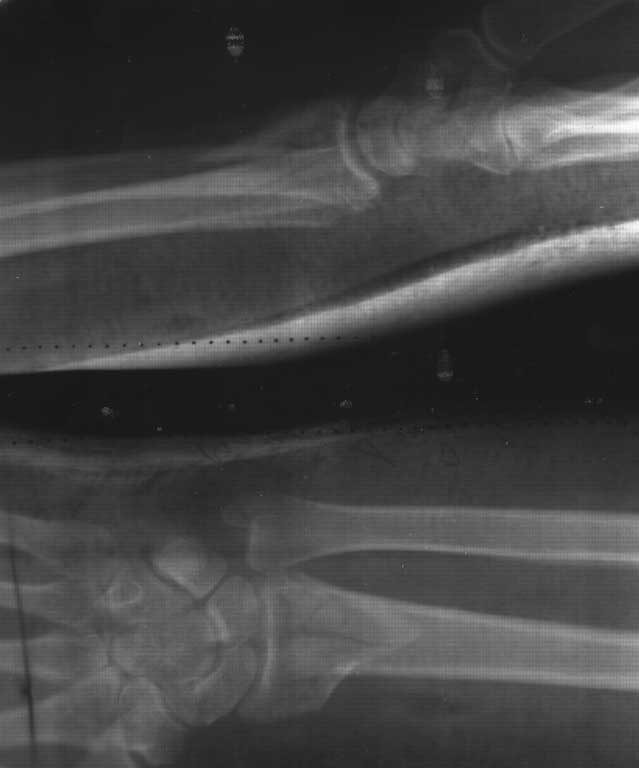

> Имеется пациентка Ч. 42 лет. 20 мая 2012 года- перелом метаепифиза левой

> лучевой кости, со смещением отломков. После репозиции стояние отломков

> удовлетворительное. 10 июня 2012 - Р-контроль, имеется смещение отломков (

> снимки прилагаются).

Укорочение лучевой кости вызвало нарушение правильных взаимотношений

дистального лучелоктевого сустава, что в дальнейшем приведет к значимому

нарушению функции предплечья, восстановление которой явялется главной

задачей. Это определеяет и выбор тактики лечения.